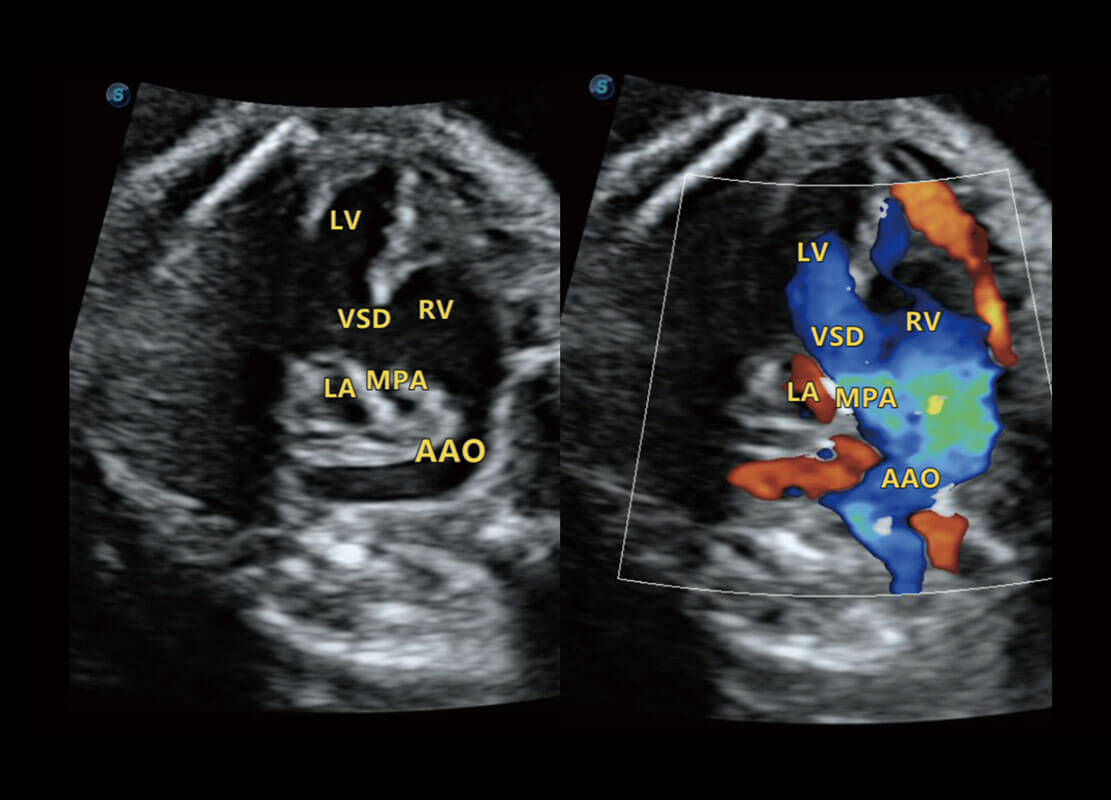

P60搭載一系列胎兒心臟成像技術(shù),實現(xiàn)精細的胎兒心臟評估。

四腔切面

四腔心血流

右室雙出口